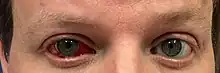

Other common complications include high intraocular pressure, bleeding in the eye, and retinal edema, swelling in the back of the eye.[12] In most cases, the retinal edema can be managed with over-the-counter medication. In severe cases, this swelling can be treated with intra-ocular injections.[13]

More severe complications after a vitrectomy are endophthalmitis (inflammation of the fluids in the eye) or suprachoroidal hemorrhage (bleeding above the choroidal layer of the eye). Rates of these complications have been reported to be less than 0.5%.